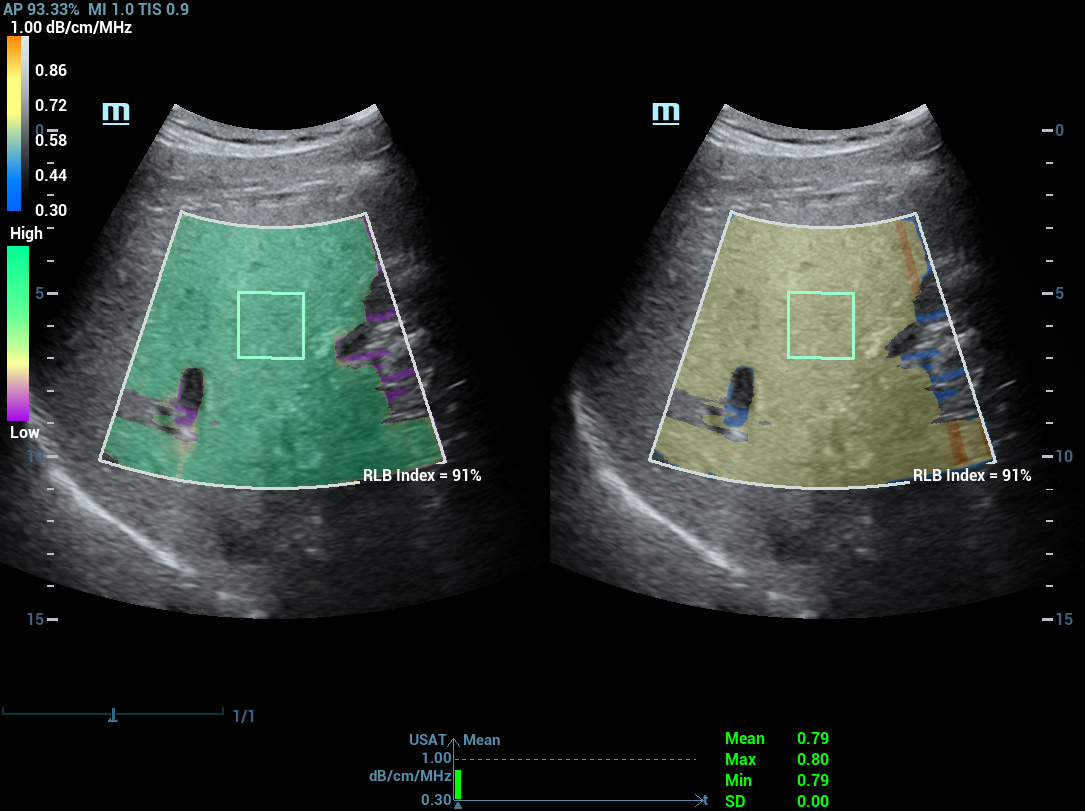

USAT (Ultrasound Attenuation Analysis Tool) оценивает степень стеатоза по коэффициенту затухания ультразвука в тканях печени. Анализ выполняется автоматически: система выбирает область интереса и проводит одно- или многократные измерения с усреднением результатов. Такой подход делает оценку стеатоза объективной и воспроизводимой.

Метод количественного анализа затухания ультразвуковой волны позволяет объективно определить содержание жира в печени. Автоматически рассчитывается коэффициент затухания и индекс RLB, отражающий степень стеатоза